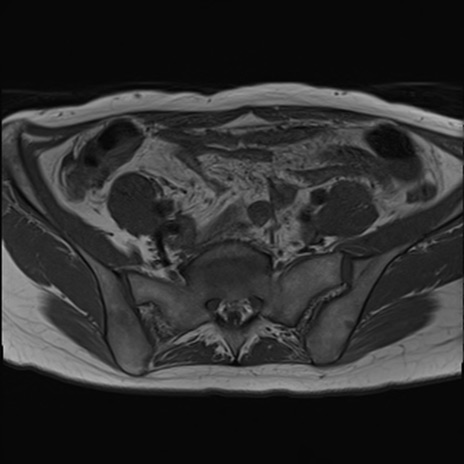

症例39 T1WI(横断像)

MRI(4日後)